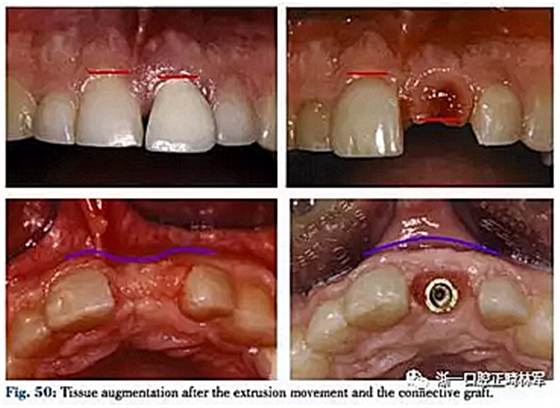

4月后在最終修復(fù)前使用臨時冠擠壓齦乳頭(圖48,49)。

通過GOR再生軟硬組織的方法與其他單純再生手段相比優(yōu)點如下:首先可以有效利用無保留價值的牙,此外該過程能同時矯正牙列,采用舌側(cè)矯治器可以允許唇側(cè)同時應(yīng)用其他輔助裝置來避免因牙齒缺失等造成的美觀問題,其消除拔牙后的軟組織塌陷,能在無需植入的情況下修復(fù)折裂及吸收牙,同時簡化了后續(xù)的治療流程(圖50)而由于不可吸收膜及正畸牽引的緩慢性,治療時間長是其缺點。